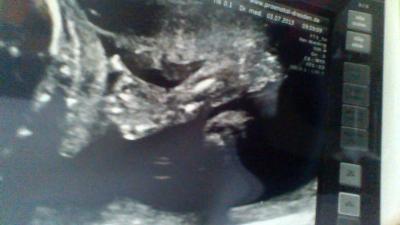

Mit dem Kleinen ist alles Bestens. Ca.25cm und 440g und besonders große Füße hat unser Kleiner auch. Kommt wohl ganz nach der Mama, die hat ja auch ne 41-42. Gab überhaupt keinerlei Auffälligkeiten und auch die Versorgung der Kindes ist super. Der Arzt war auch super nett und sogar das Gel war angewärmt. Und ich weiß jetzt warum ich immer nur rechts tritte vom Würmchen kriege, weil meine VWP links liegt. Bin total verliebt in unseren kleinen Wurm und der Papa auch. Hier zeigt uns der Kleine das alles mit Ihm okay ist:

Bild zu FD-Ergebniss - Forum für November - Mamis